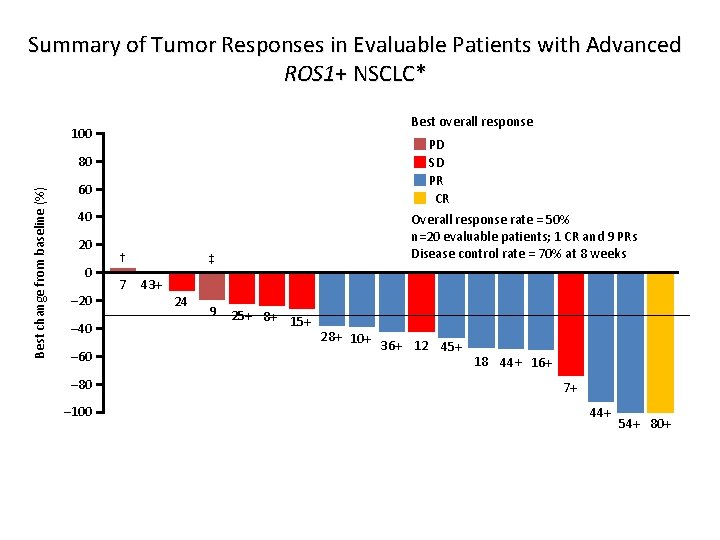

Summary of Tumor Responses in Evaluable Patients with Advanced ROS 1+ NSCLC* Best overall response 100 PD SD PR CR Best change from baseline (%) 80 60 40 20 0 – 20 – 40 – 60 – 80 – 100 † 7 Overall response rate = 50% n=20 evaluable patients; 1 CR and 9 PRs Disease control rate = 70% at 8 weeks ‡ 43+ 24 9 25+ 8+ 15+ 28+ 10+ 36+ 12 45+ 18 44+ 16+ 7+ 44+ 54+ 80+